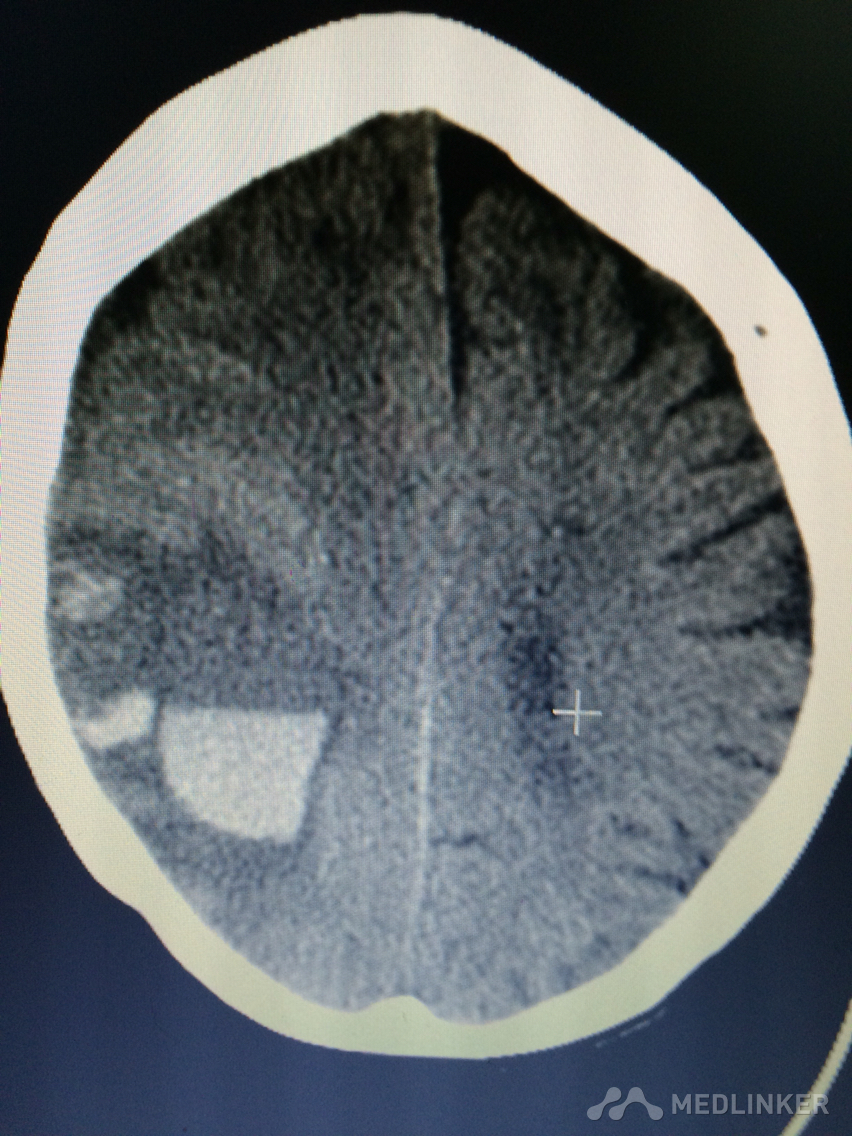

下面的CT考虑?

1天前,患者睡醒后出现反应迟钝,认知功能障碍,左侧肢体乏力。 既往无高血压病史,近期无外伤史。